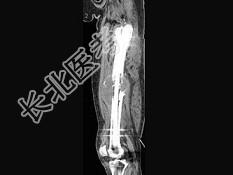

- 单项选择题男,18岁, 右股骨肿瘤术后,出现大腿中段疼痛, 夜间尤甚,结合CT图像, 最可能的诊断是 ( )